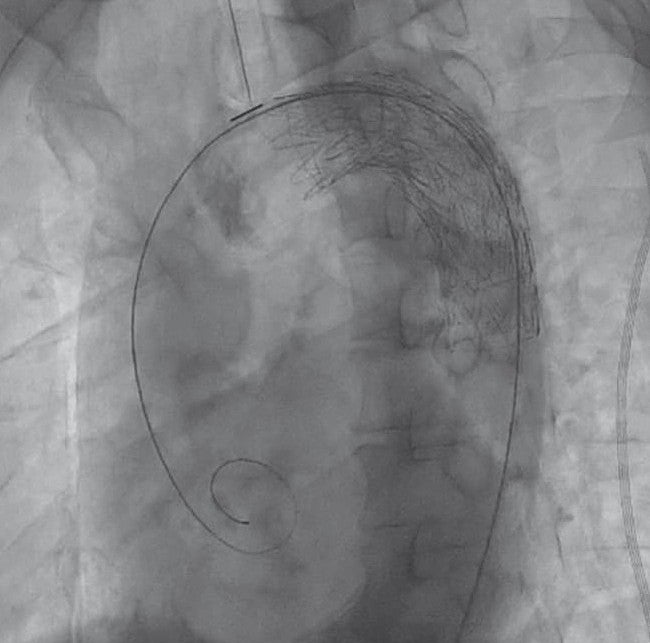

全身麻酔下、仰臥位にて手術を開始した。右鼠径部を切開し、右総大腿動脈をテーピング、タバコ縫合をおいた。ヘパリン投与後、右総大腿動脈から5 Frシースを挿入した。右総大腿動脈シースからピッグテールカテーテルを上行大動脈まで進め、ステントグラフト用ガイドワイヤーに変更、シースを20 Frゴア® ドライシール フレックス イントロデューサシースに入れ替えた。デバイスは末梢側からTAG® コンフォーマブル ステントグラフト28 mm × 10 cm、および31 mm × 10 cmを選択した。まず28 mm × 10 cmを左鎖骨下動脈末梢から留置、ついで31 mm × 10 cmを予定留置部位まで進め、造影で左総頚動脈および左鎖骨下動脈の位置を確認し、アンギュレーションコントロールダイヤルをゆっくり回しながらデバイス中枢の角度を慎重に大動脈に合わせた後に留置した。解離症例であるためバルーンによる圧着は施行せず、最終造影でエンドリークを含め異常のないことを確認し手技を終了した。手術時間は1時間11分であった。

術後CTでは明らかなエンドリークはみられず経過良好で術後6日目に退院、引き続き外来で経過観察中である。